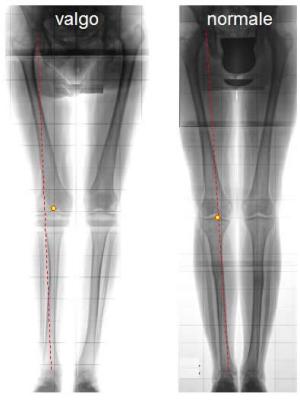

L’interpretazione di tale problematica è molto complessa; alla base della sintomatologia vi è un problema dell’allineamento rotuleo rispetto alla troclea femorale; la rotula infatti scorre nella sua sede ad ogni flesso-estensione di ginocchio, e se tale meccanismo non avviene alla perfezione si ha un maggior consumo cartilagineo rispetto alla norma. fisioterapia angolo QIl malallineamento rotuleo è talvolta evidenziabile dall’aumento dell’angolo che si forma tra l’asse diafisario del femore e l’asse diafisario della tibia, ma non è l’unico fattore predisponente; ha infatti un’enorme importanza l’atteggiamento rotazionale di femore e quello della tibia; infatti la rotazione interna del femore e la rotazione esterna della tibia predispongono ad un’aumento della compressione tra rotula e femore nella parte rotulea esterna.